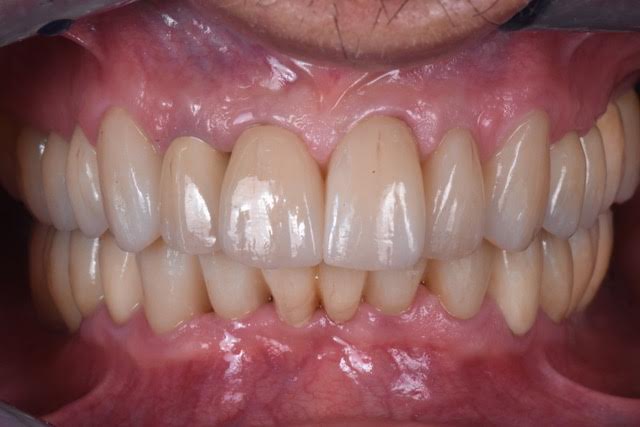

Riabilitazione implanto-protesica completa di paziente disfunzionale, con molteplici fratture ed abrasioni.